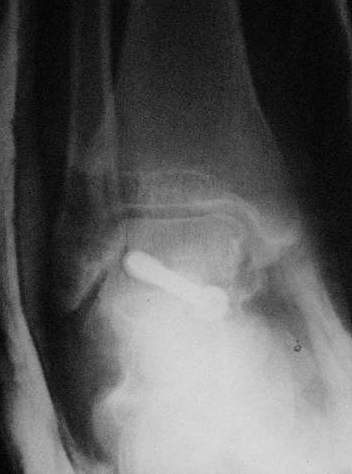

Переломовывих тарана с повреждением медиальной стороны. Через 4 часа после поступления проведена репозиция и фиксация тарана после Irrigation&Debridment. Частичное несращение медиальной лодыжки не беспокоит, вернулся к активному образу жизни. Полная нагрузка разрешена через 11 недель. Финальные снимки через 11 месяцев.

Из-за многооскольчатости дистальной части малоберцовой, где невозможно было провести фиксацию шурупами, перелом зафиксирован подпирающей пластиной, которая должна служить дополнением отсутствующей дистальной части малоберцовой (lateral cortex substitute).

Для стабильности два шурупа на синдесмоз.

Медиальную рану с приближенными краями продолжаем вакуумировать (KCI). Наружный фиксатор оставлен на пару недель, надеюсь, небольшая рана будет гранулировать и закроется без кожной пластики. Фиксация медиальной ложыжки не планируется.